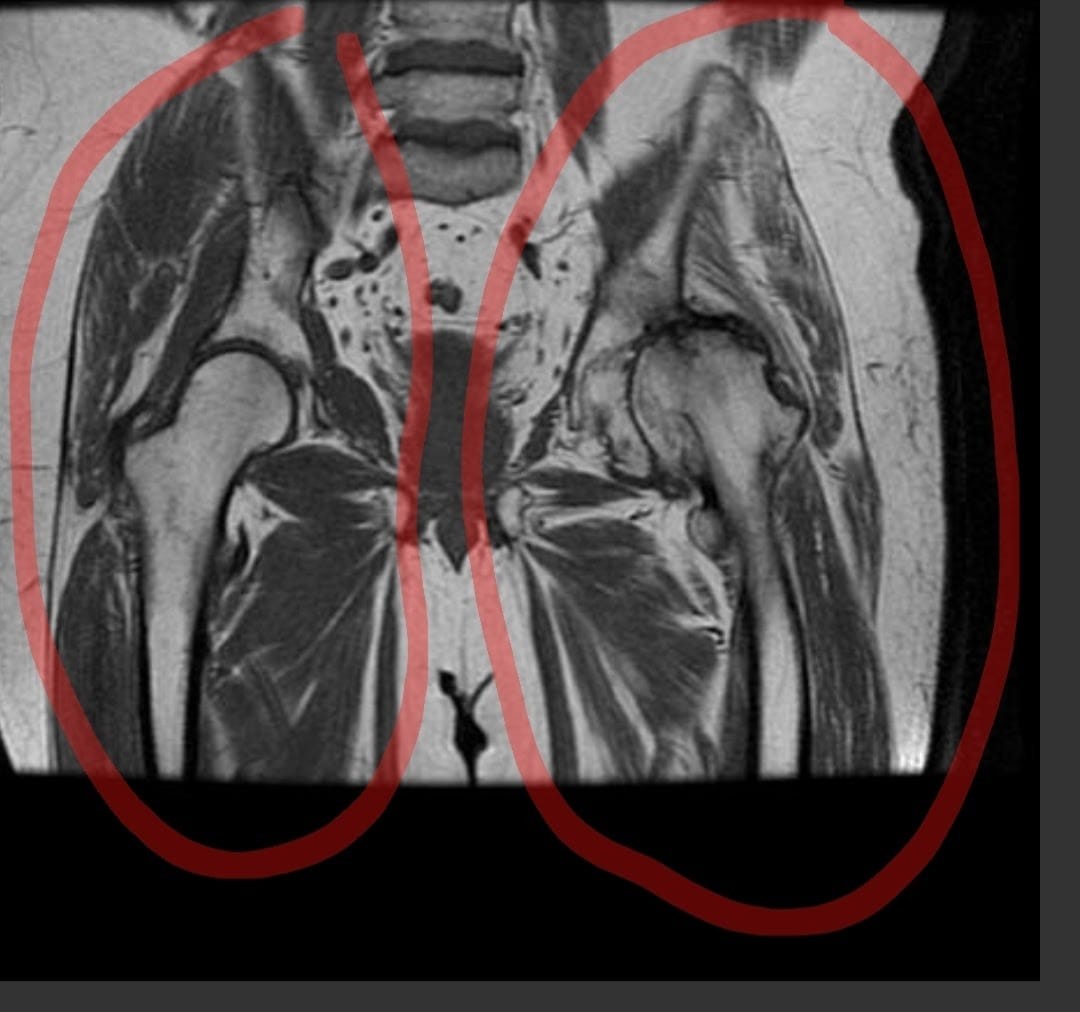

«Mi historia comienza cuando me afilié a la prepaga Crystal Medicina Privada, pagando puntualmente la cuota todos los meses. Mi médico y yo decidimos que necesitaba una operación, pero para realizarla, requería la autorización de la prepaga. En marzo, presenté todos los papeles y estudios necesarios, incluyendo la resonancia magnética nuclear.